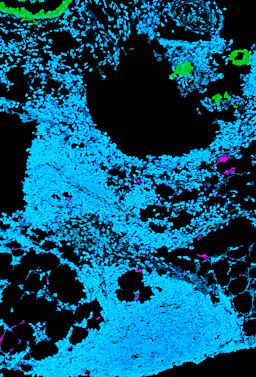

Pancreatic ductal adenocarcinoma is a lethal disease with limited treatment options and poor survival. We studied 83 spatial samples from 31 patients (11 treatment-naïve and 20 treated) using single-cell/nucleus RNA sequencing, bulk-proteogenomics, spatial transcriptomics and cellular imaging. Subpopulations of tumor cells exhibited signatures of proliferation, KRAS signaling, cell stress and epithelial-to-mesenchymal transition. Mapping mutations and copy number events distinguished tumor populations from normal and transitional cells, including acinar-to-ductal metaplasia and pancreatic intraepithelial neoplasia. Pathology-assisted deconvolution of spatial transcriptomic data identified tumor and transitional subpopulations with distinct histological features. We showed coordinated expression of TIGIT in exhausted and regulatory T cells and Nectin in tumor cells. Chemo-resistant samples contain a threefold enrichment of inflammatory cancer-associated fibroblasts that upregulate metallothioneins. Our study reveals a deeper understanding of the intricate substructure of pancreatic ductal adenocarcinoma tumors that could help improve therapy for patients with this disease.